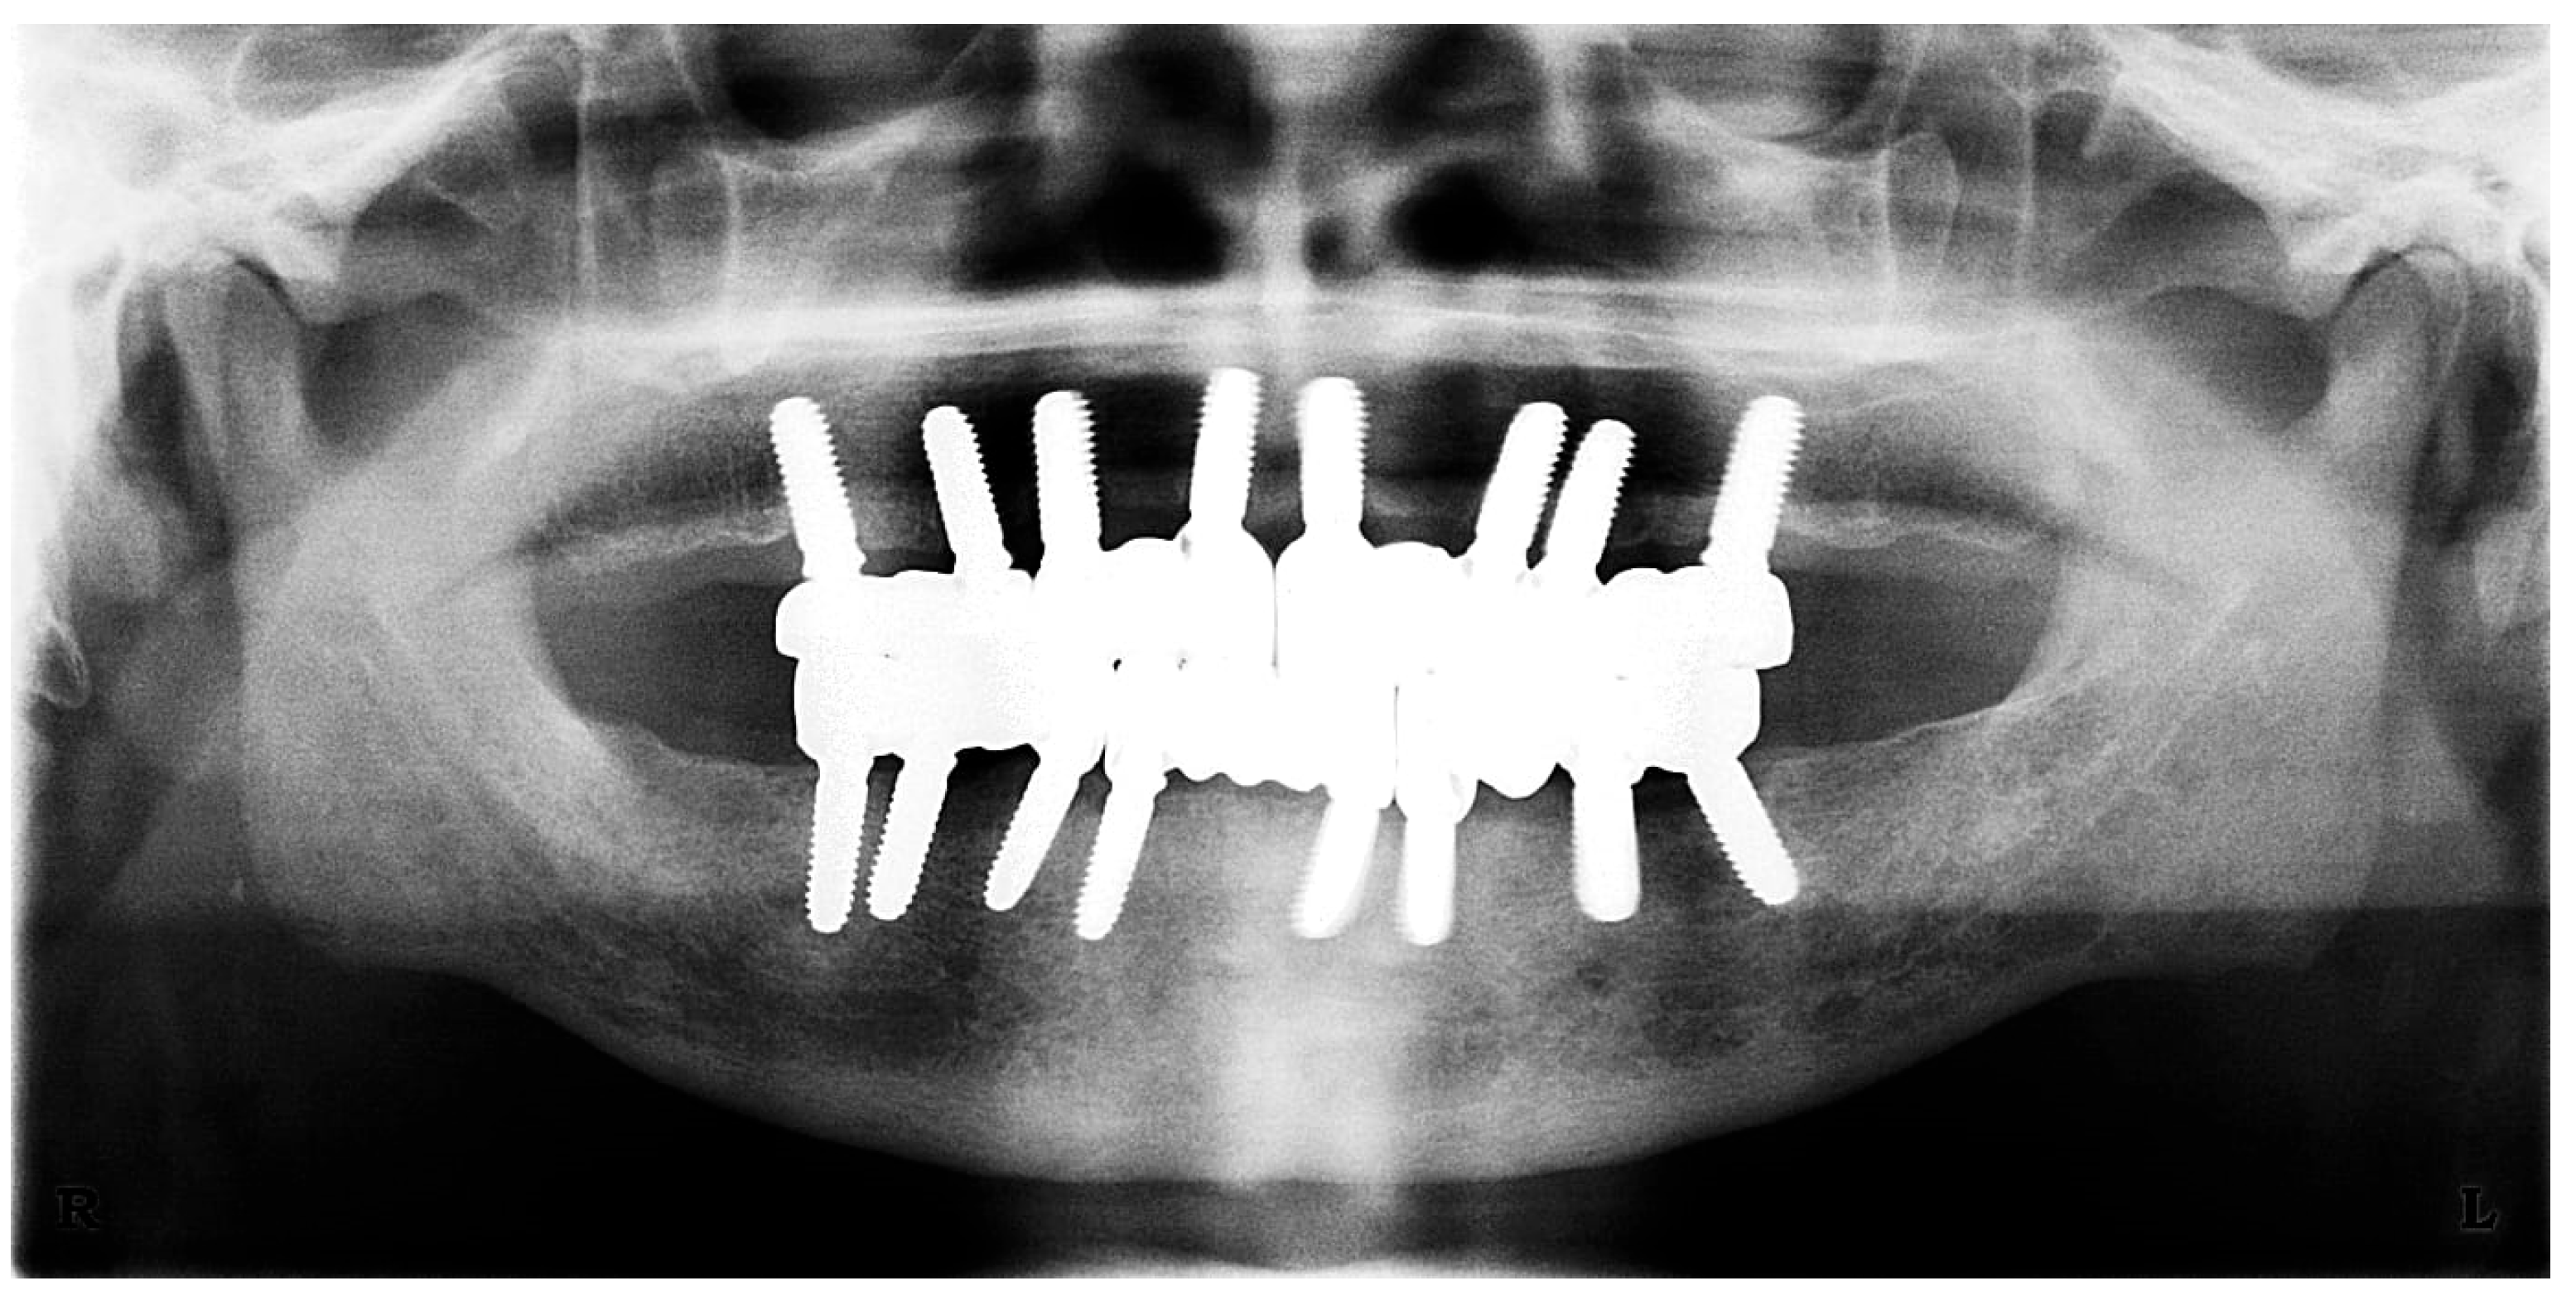

Figure 17. Panoramic X-ray at follow-up visit (taken 9 September 2025).

2.6. Sixth Visit

During the three-year follow-up period from October 2022 through September 2025, the patient was regularly recalled for evaluation. The peri-implant soft tissues remained healthy throughout the observation period. The gingiva surrounding the implants was consistently pink, firm, and showed no bleeding or suppuration upon probing of the peri-implant sulcus. At the last visit, probing depths ranged from 2–4 mm (mean 3 mm) in the maxillary arch and 1–3 mm (mean 2 mm) in the mandibular arch. No clinical signs of inflammation, edema, or granulation tissue were observed, indicating stable peri-implant mucosa and sustained biocompatibility of the materials used. Radiographic assessment revealed no crestal bone loss, and the prosthetic components remained functionally and esthetically intact, with no evidence of wear, fracture, or loosening. The patient reported high satisfaction regarding comfort, function, and appearance, further supporting the clinical success and reliability of this treatment approach (Figure 16 and Figure 17).